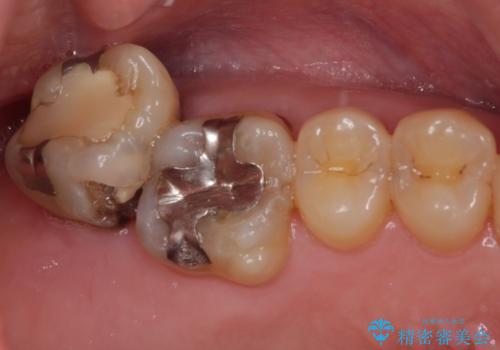

上顎の奥歯は、左右ともに外側に転位しており、特に右上はむし歯の範囲が広く、根管治療も必要な状態でした。

上顎左右の歯をアンカースクリューを用いた部分矯正により位置を修正し、オールセラミッククラウンにて補綴治療を行うこととしました。